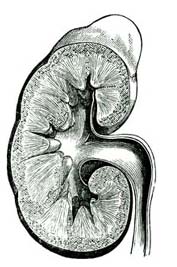

8. Poison in the Breath.—The burning which takes place in our bodies produces something [Pg 65]similar to the smoke and ashes produced by the fire in a stove. The smoke is called carbonic-acid gas,[A] an invisible vapor, and escapes through the lungs. The ashes are various waste and poisonous matters which are formed in all parts of the body. These waste matters are carried out of the body through the skin, the kidneys, the liver, and other organs.